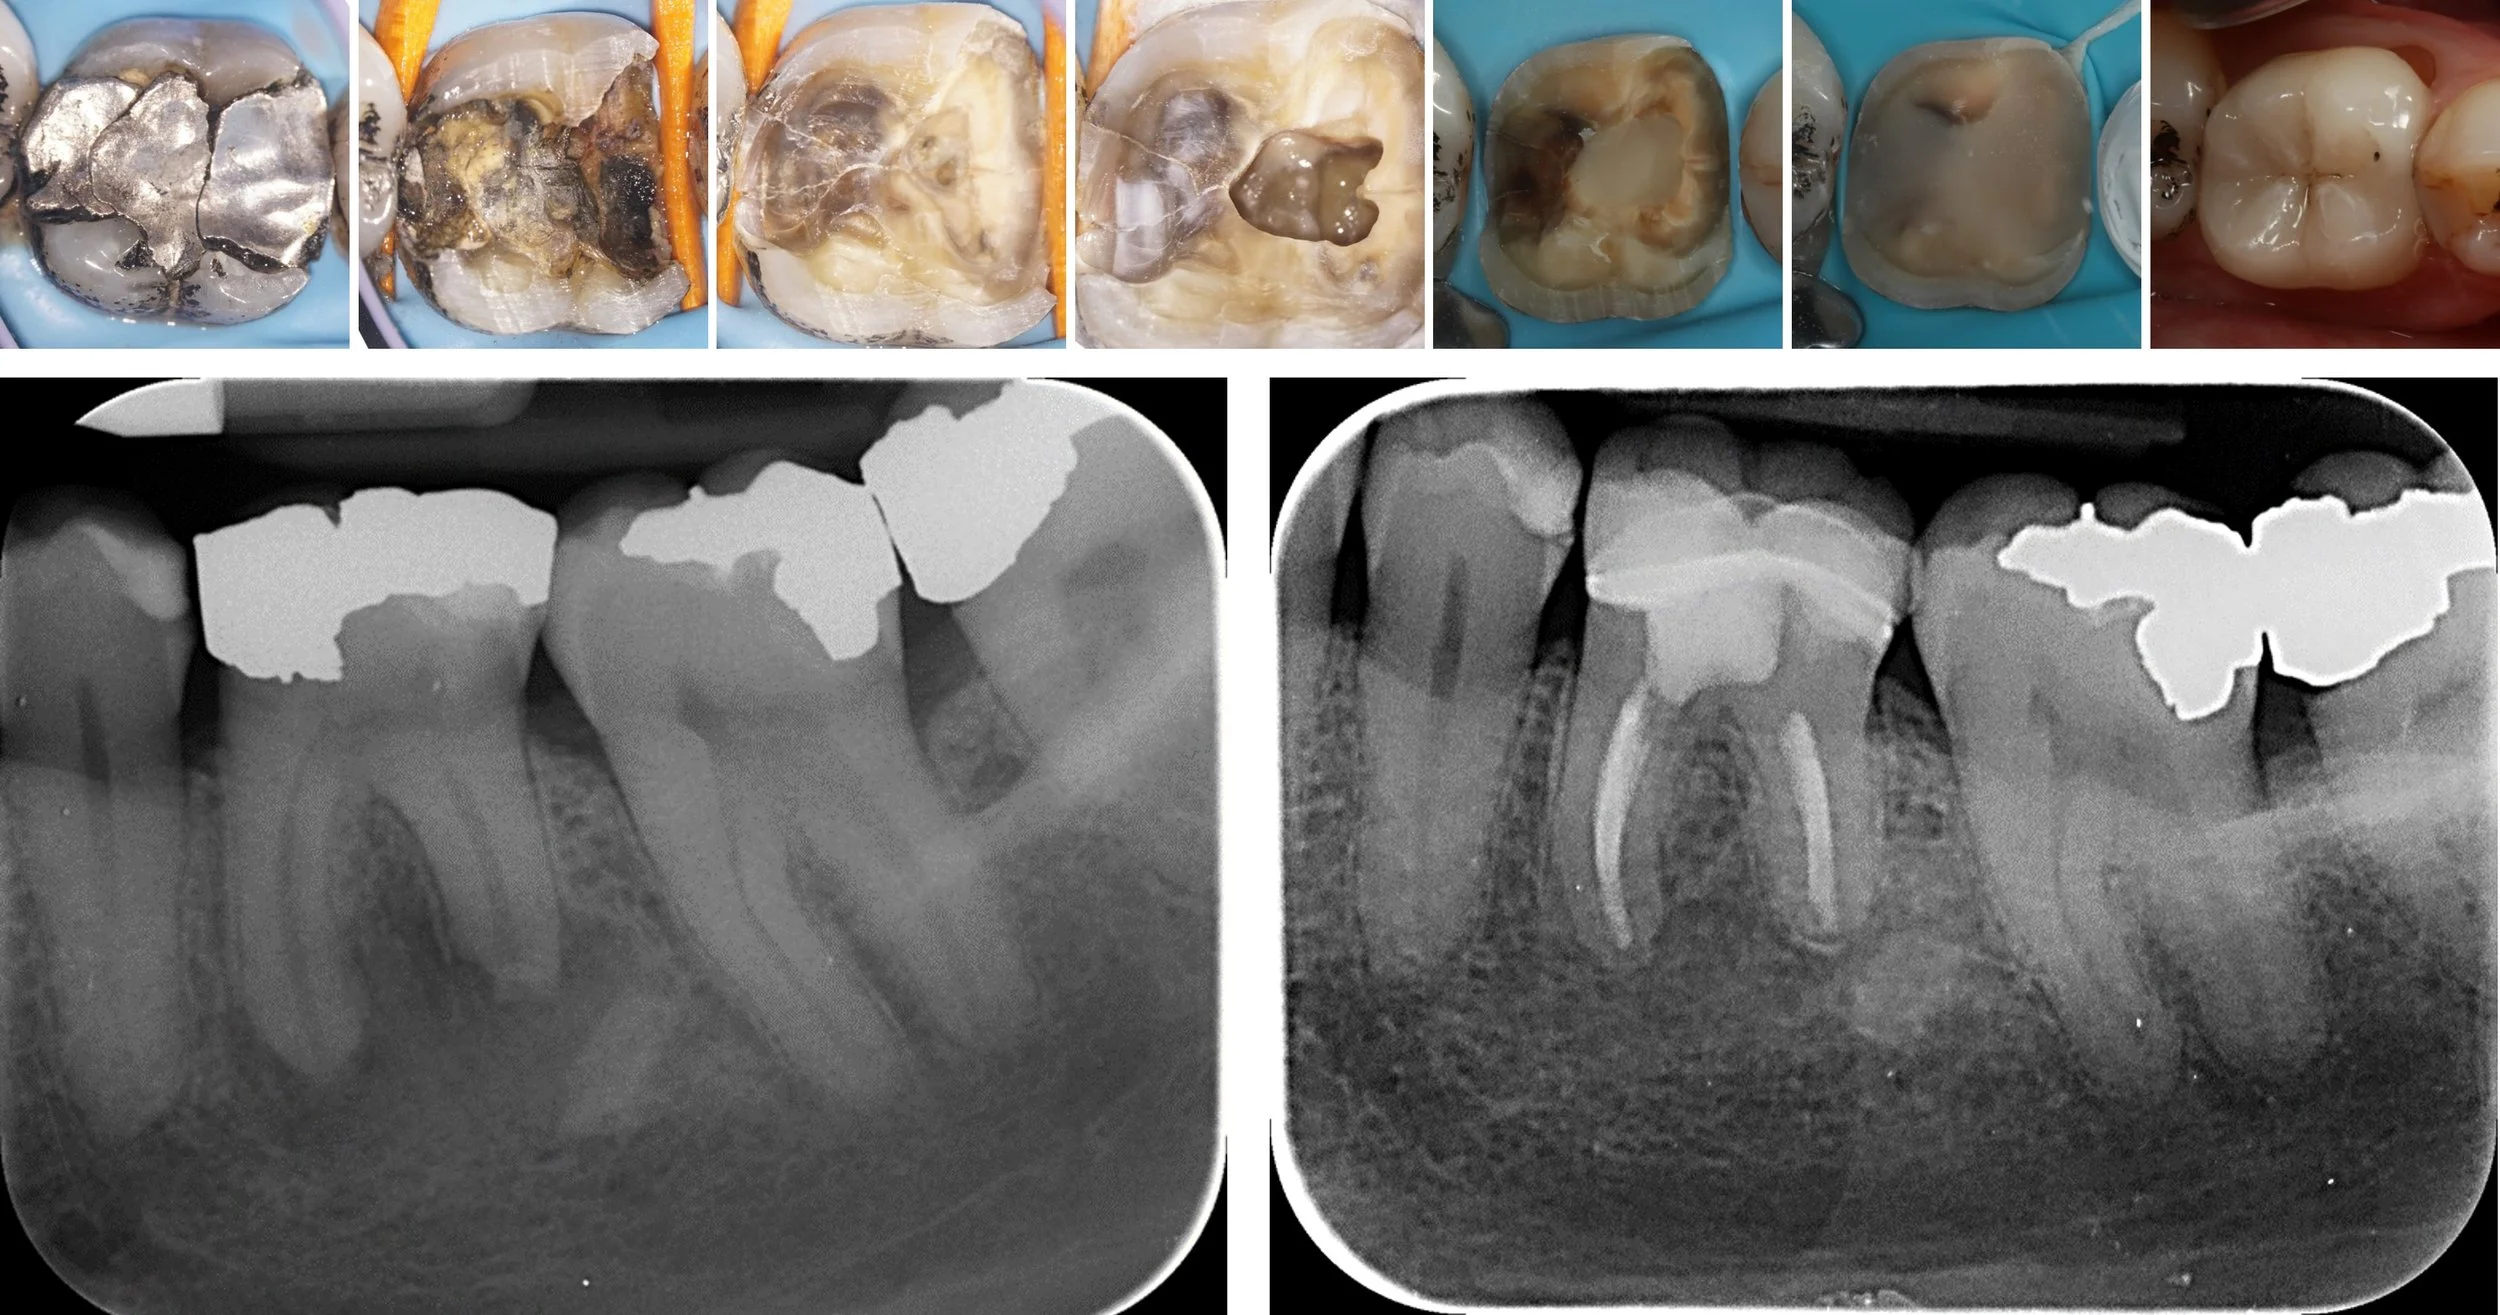

Precision root canal treatment under microscope.

All procedures completed under operating microscope — using the latest evidence-based techniques and premium materials for outcomes that last.